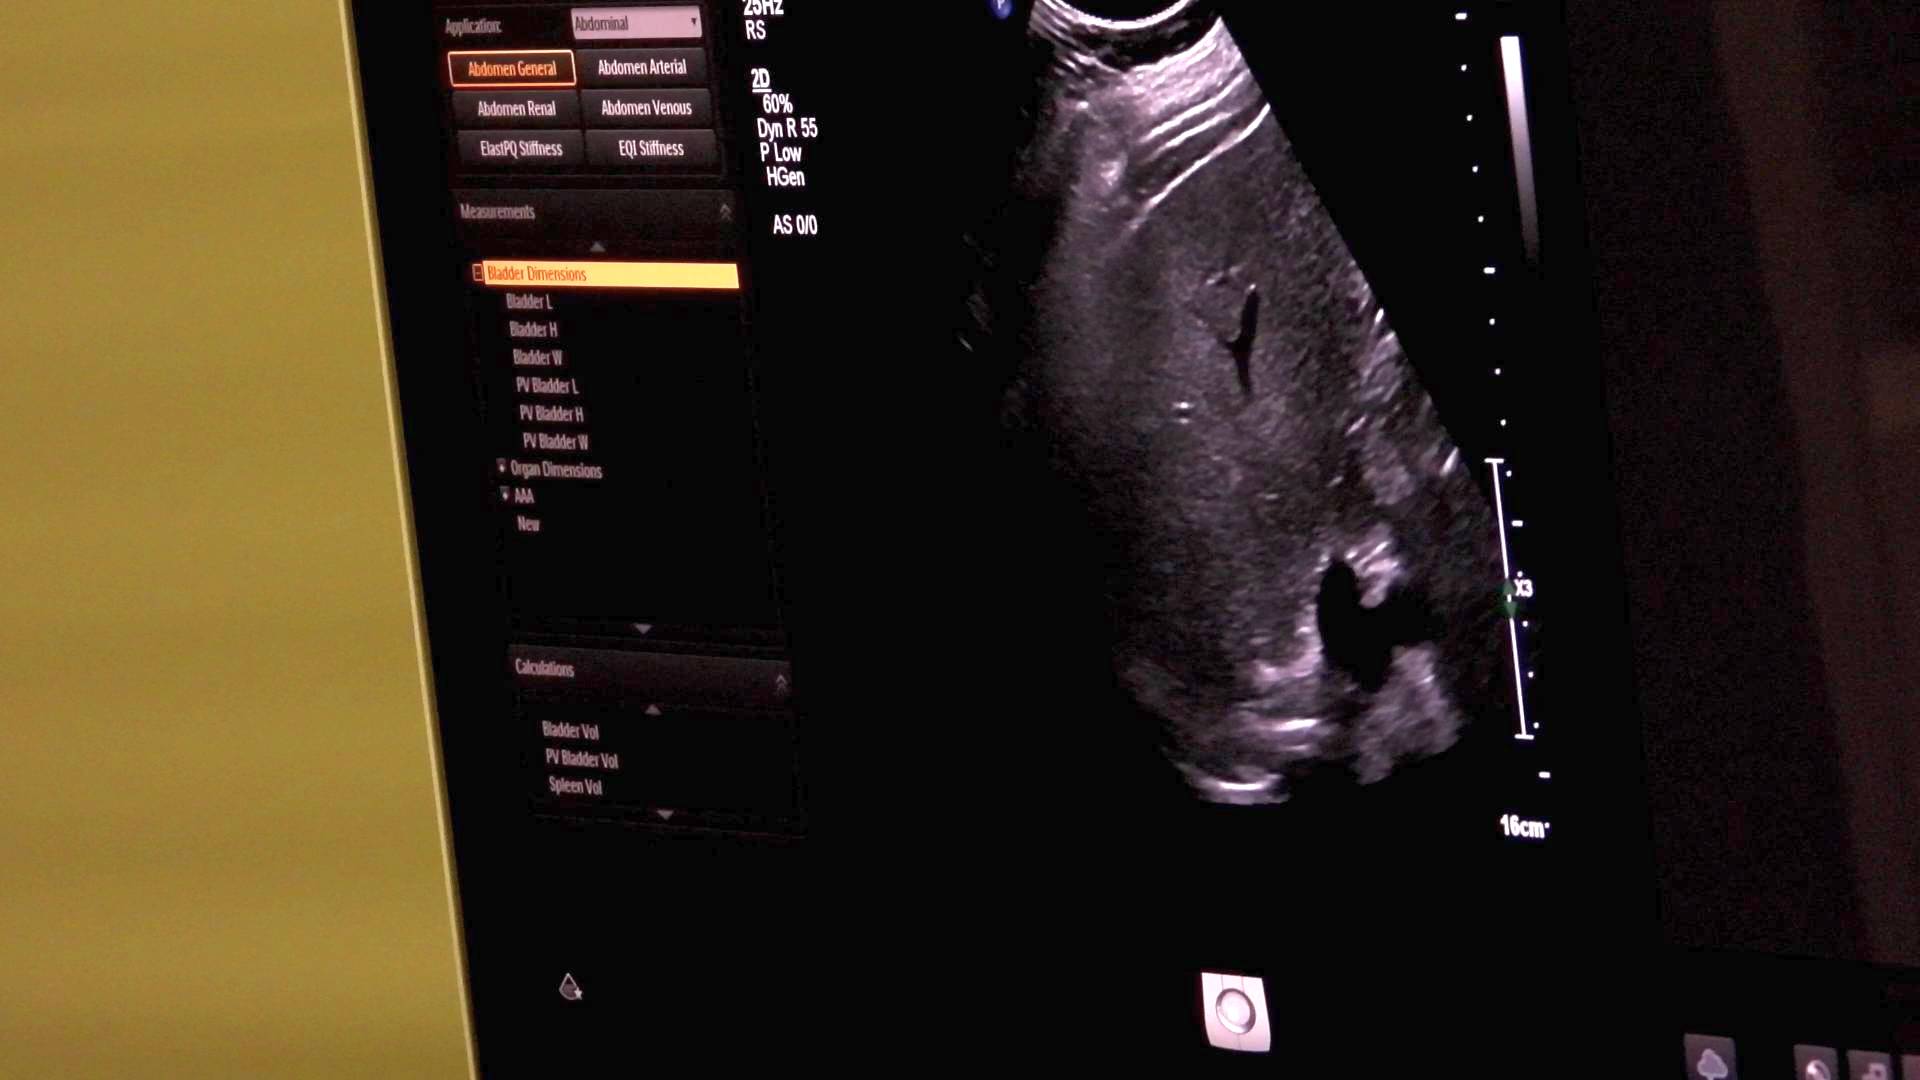

Tokom tri sedmice pregleda obavljenih u Edukacijskom centru KBZ-a, detaljnim pregledima je pristupilo 200 građana. Ultrazvuk abdomena je brz, bezbolan i siguran način da se provjeri stanje unutrašnjih organa, poput jetre, bubrega, gušterače i žučne kese.

Ultrazvuk abdomena je jednostavna, bezbolna i sigurna metoda pregleda pomoću koje možemo pregledati organe i strukture koji se nalaze unutar trbušne šupljine. Ovaj pregled igra važnu ulogu u ranom otkrivanju promjena koje mogu dovesti do narušavanja zdravlja i razvoja bolesti.

Mnoga stanja, poput kamenaca u žuči ili bubrezima, cisti, tumora, masne jetre, ne pokazuju simptome u ranim fazama. Ultrazvuk može otkriti ove promjene na vrijeme, prije nego što dođe do simptoma bolesti. Rano otkrivanje tumora ili vaskularnih promjena značajno povećava šanse za uspješno liječenje i oporavak. Prikaz šupljih organa (želudac i crijeva) abdominalnim ultrazvukom otežan je zbog prisutnosti zraka te se za njihov prikaz koriste druge pretrage, kao što su endoskopski ultrazvuk te gastroskopija i kolonoskopija.